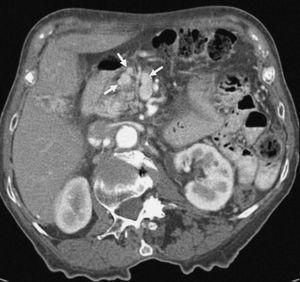

Aunque algunos autores no han observado diferencias significativas en cuanto al rendimiento de la TC helicoidal monofásica y bifásica en la detección y estadificación del cáncer de páncreas13, otros autores19,32, en series más largas incluyendo un mayor número de pacientes con tumores resecables, han aseverado el rendimiento de la TC helicoidal bifásica en la predicción de la resecabilidad del cáncer de páncreas, presentando valores predictivos para la resecabilidad tumoral entre 73,5% y 77% y valores de precisión diagnóstica entre 77% y 83%. Revisando específicamente los signos TC de infiltración vascular mediante TC helicoidal bifásica, Lu et al33, utilizando un sistema de gradación basado en la contigüidad del tumor con cada una de las estructuras vasculares (venas porta y mesentérica superior, o arterias hepática, mesentérica superior y tronco celíaco), presentaron un valor predictivo positivo del 95% y un valor predictivo negativo para la irresecabilidad neoplásica del 93% cuando consideraban infiltración vascular una contigüidad del tumor que excedía el 50% de la circunferencia del vaso en cuestión (fig. 4). A este mismo respecto Phoa et al34 describen como criterios de TC más fiables de invasión venosa la estenosis e irregularidad de la vena porta o la vena mesentérica superior, así como una contigüidad circunferencial del tumor con la vena porta superior a 90º (fig. 5). Los autores concluyen que la mejor combinación de criterios de TC fue la concavidad tumoral con afectación circunferencial vascular, con lo que presentan una sensibilidad del 61% y especificidad del 90%. Hough et al35 describieron el signo de la lágrima de la vena mesentérica superior, que consiste en una deformidad de la morfología redondeada de la vena adyacente al tumor en las secciones axiales, como indicativo de invasión venosa (fig. 6). Añadiendo este signo a los ya descritos de invasión venosa, consiguen aumentar la sensibilidad (60-91%) y el rendimiento diagnóstico de la TC (79-95%) sin modificar significativamente la especificidad (100-98%). No obstante, estos sistemas de gradación para el diagnóstico de la invasión vascular peripancreática tienen el inconveniente de la subjetividad a la que está sometida su lectura. Los casos extremos no presentan problemas de interpretación, pero la valoración del tumor rodeando al vaso alrededor de 90º de su circunferencia puede ser difícil, dado que además pueden existir bandas de infiltración de la grasa peripancreática que pueden rodear parcialmente un vaso o incluso continuarse sin plano graso de separación con el tejido tumoral. Estas bandas pueden representar cambios edematosos o inflamatorios locales (fig. 7). En este sentido, Valls et al19,36 presentan únicamente un 25% de valor predictivo positivo para la irresecabilidad tumoral para estas bandas perivasculares. Además se ha descrito la notoria variabilidad interobservador en función de su experiencia, que llega a alcanzar una diferencia de sensibilidad de hasta un 20% entre revisores experimentados y noveles14.

Fig. 5.--Adenocarcinoma de páncreas. Estudio de tomografía computarizada con contraste endovenoso en fase pancreatográfica. Masa de 5 cm al nivel de la cabeza pancreática que contacta ampliamente con la vena mesentérica superior (VMS) en aproximadamente 50° de su circunferencia, sin deformarla ni disminuirla de calibre. En la intervención quirúrgica se confirmó la invasión de la VMS, realizándose resección con interposición de injerto venoso.